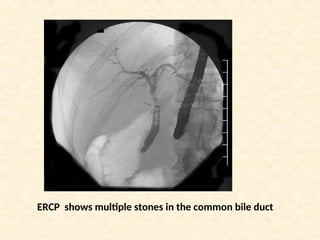

ERCP shows multiple stones in the common bile duct

ERCP shows multiplestones in the common bile duct